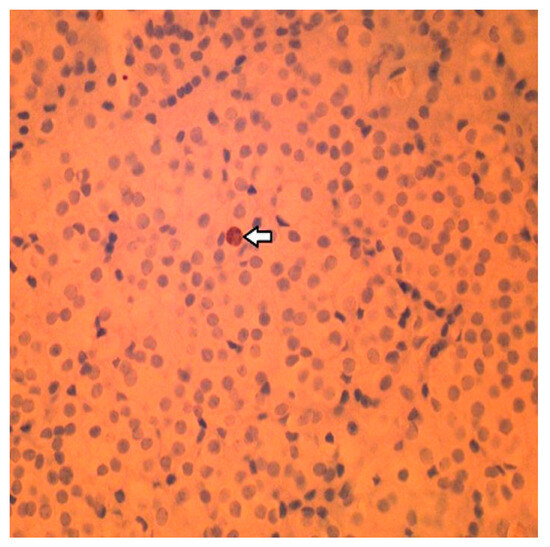

2.4. Histology